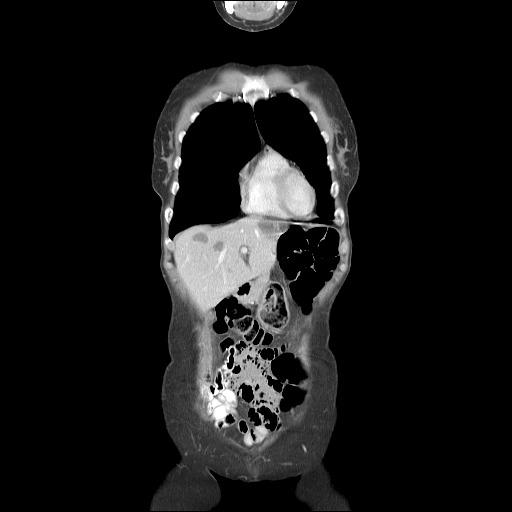

Hepatic hemangiomas are benign tumors of the liver consisting of clusters of blood-filled cavities, lined by endothelial cells, fed by the hepatic artery. The vast majority of HH are asymptomatic, most often being discovered incidentally during imaging investigations for various unrelated pathologies. Typical hemangiomas, the so-called capillary hemangiomas, range from a few mm to 3 cm, do not increase in size over time and therefore are unlikely to generate future symptomatology. Small (mm-3 cm) and medium (3 cm-10 cm) hemangiomas are well-defined lesions, requiring no active treatment beside regular follow-ups. However, the so-called giant liver hemangiomas, of up to 10 cm (most commonly) and even 20+ cm in size (according to occasional reports) can, and usually will develop symptoms and complications that require prompt surgical intervention or other kind of therapy. HH belong to the class of hepatic "incidentalomas", so-called because they are diagnosed incidentally, on imaging studies performed as routine examinations or for other reasons than the evaluation of a possible liver mass. Less than half of HH present with overt clinical symptoms, consisting, most often, of upper abdominal pain (this is usually the case for large lesions, which cause the distension of Glisson's capsule). Hepatic hemangiomas require a careful diagnosis to differentiate from other focal hepatic lesions, co-occurring diagnoses are also possible.